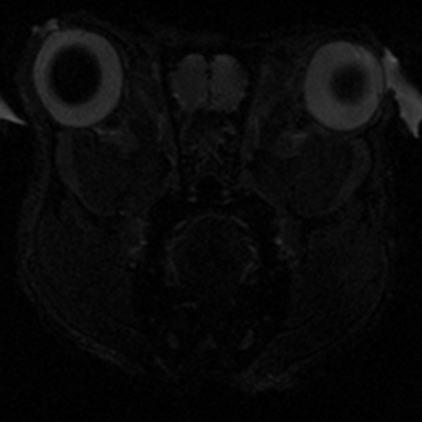

Yüksek sinyal (SNR) ve güçlü gradyan sargıları ile daha yüksek uzamsal çözünürlük ile görüntüleme yapılmasına olanak tanır. Böylece daha deney hayvanlarında çok daha olan küçük anatomik yapılar ve bunların detayları daha net görülür, bu da beyin, kalp, batın ve kas-iskelet yapılarının görüntülenmesinde sistemi özellikle değerli kılar.

7T MRG tarayıcısının sağladığı yüksek doku görüntü kontrastı organlardaki farkı doku tipleri ve dokulardaki varyasyonları ayırt etmek için önemlidir. Bu, özellikle nöro-görüntülemede örneğin hipokampüs ve bazal ganglia gibi yapılar için avantaj sağlar.

• T1 ve T2 ağırlıklı görüntüleme (beyin, organ, tümör, ...)